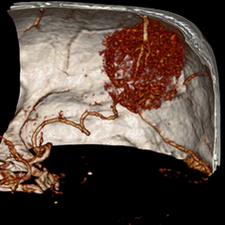

标题: CT25808:男,48岁,头痛多年,近段时间头痛加重伴步态不稳 [打印本页]

标题: CT25808:男,48岁,头痛多年,近段时间头痛加重伴步态不稳

平扫:右颞顶叶病灶呈等低密度伴大面积水肿,脑室受压变形。增强:病灶显著强化。考虑淋巴瘤或黑色素瘤。